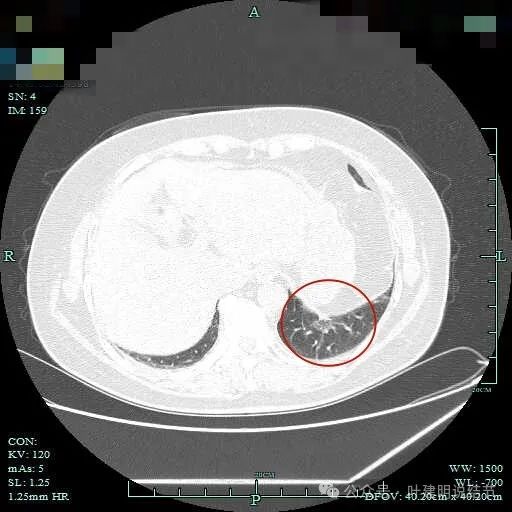

边缘略显糊,与膈肌贴着。

远侧端有阻塞性炎症的表现,病灶在些层也是磨玻璃密度。

边缘区域略显轮廓不清。